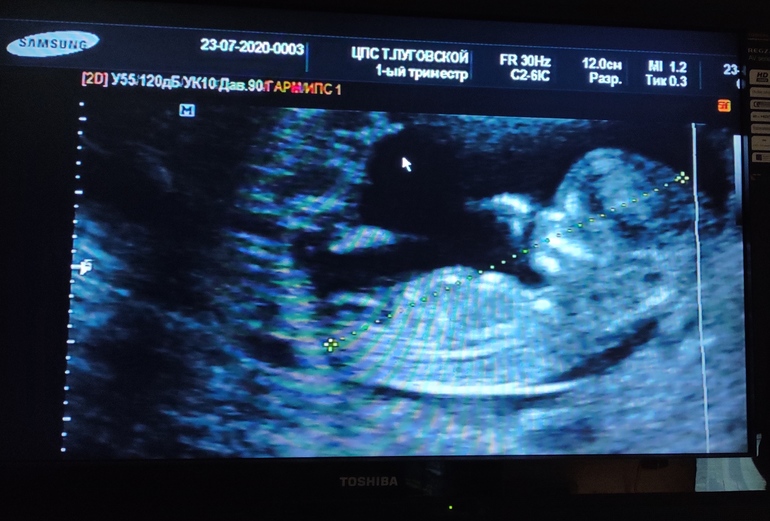

Скрининг _12 недель.

УЗИ, КТГ, доплерСделала УЗИ - все хорошо.

Соответствует сроку).

ПДР - 03.02.21г.

Мышка очень активная).

Серцебиение - 162 удара.

Пол - Сказала : - " Явного мальчика не вижу.

Бугорок по которому опрелеляют, у мальчика вертикально, у девочки - горизонтально. У вас - горизонтально.